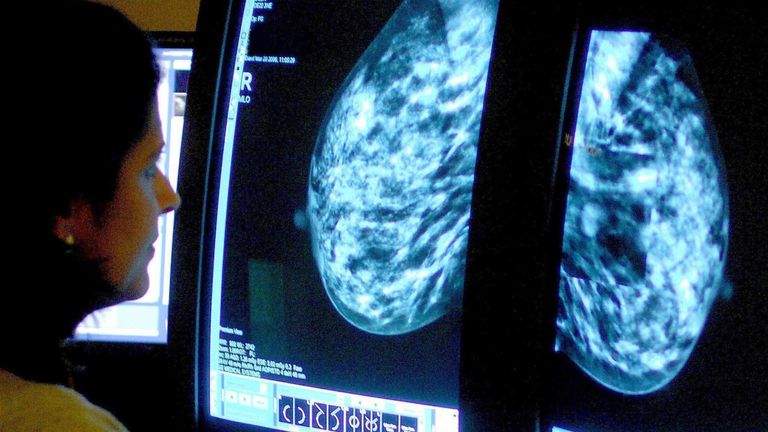

A new drug could stop some breast cancer tumours from using hormones to grow, a trial has found.

The study, funded by AstraZeneca, looked at patients with hormone-positive, HER2-negative breast cancer – about 70% of cases.

Cancer Research UK reports that breast cancer is the most common type of the disease, with around 56,400 women and around 390 men diagnosed in the UK each year.